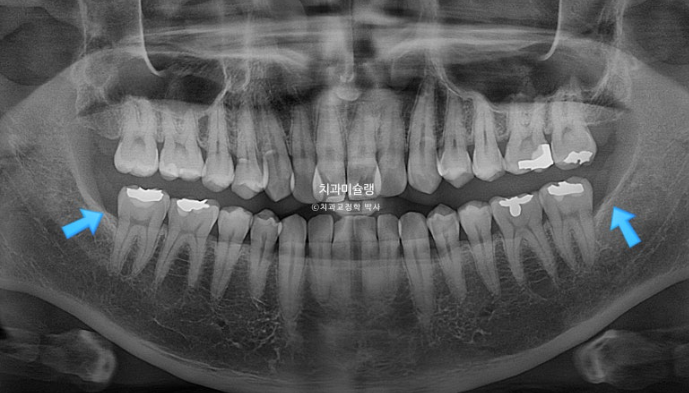

그러나 사랑니 공간이 없는 상황이라 비발치 후방이동 방법은 쓰기 어렵습니다.

30대 후반이라는 나이와 성별을 고려하면 악궁확장 실패 가능성이 커서 악궁확장장치 심는 날 봉합부를 따라 뼈를 느슨하게 만드는 corticopuncture도 함께 시행해야 합니다.

교정 후 치근흡수는 없고 뿌리 정렬상태도 좋습니다.